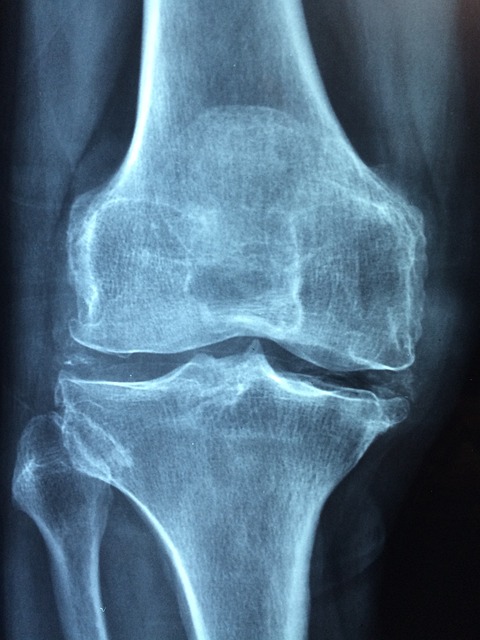

골다공증 진단에는 X선 검사와 골밀도 측정이 포함됩니다. 이러한 테스트를 통해 뼈의 건강 상태를 확인할 수 있습니다. 병리학적 검사를 통해 뼈의 밀도가 감소하는 것을 확인할 수 있으므로 골다공증 치료를 위해 진단이 우선시 되어야 합니다. 골다공증 초기치료로는 뼈 건강에 좋은 칼슘 및 비타민 D를 충분히 섭취하는 방법이 있습니다. 흔히 먹을 수 있는 우유와 유제품, 두유, 아몬드 우유, 양배추 브로콜리, 케일, 연어, 참치, 소고기, 닭고기, 계란, 아몬드, 바질씨, 견과류, 홍합, 새우, 완두콩, 건포도, 멸치 등은 칼슘이 풍부한 음식이므로 매 식사 시, 식간에 섭취하는 것이 좋으며 비타민 D 흡수를 위해 산책과 일광욕을 자주 하면 도움이 됩니다. 칼슘과 비타민 D 보충제 또한 복용할 수 있습니다. 골다공증이 심하다면 비인두 스테로이드 약물, 계승체 억제제, 이형 화합물과 같은 약물을 처방받아 사용할 수 있는데 이와 같은 약물은 뼈 손상을 줄이고 골밀도를 증가시키는 데 사용됩니다. 그러나 과도하고 지속적인 약물 복용으로 인한 부작용이 있을 수 있으니 반드시 전문가의 처방을 따라야 하며 약으로만 의존하는 것이 아니라 식품도 함께 섭취함으로써 건강하게 치료해야 합니다. 또한 흡연과 금주는 골다공증의 위험을 증가시킬 수 있으므로 제한하는 것이 좋으며 규칙적인 운동은 중요한 치료 요소 중 하나이므로 강도 있는 운동을 통해 뼈 밀도를 증가시키고 근육을 강화하는 것이 좋으며 운동 시 부딪히지 않도록 주의를 기울여야 합니다.